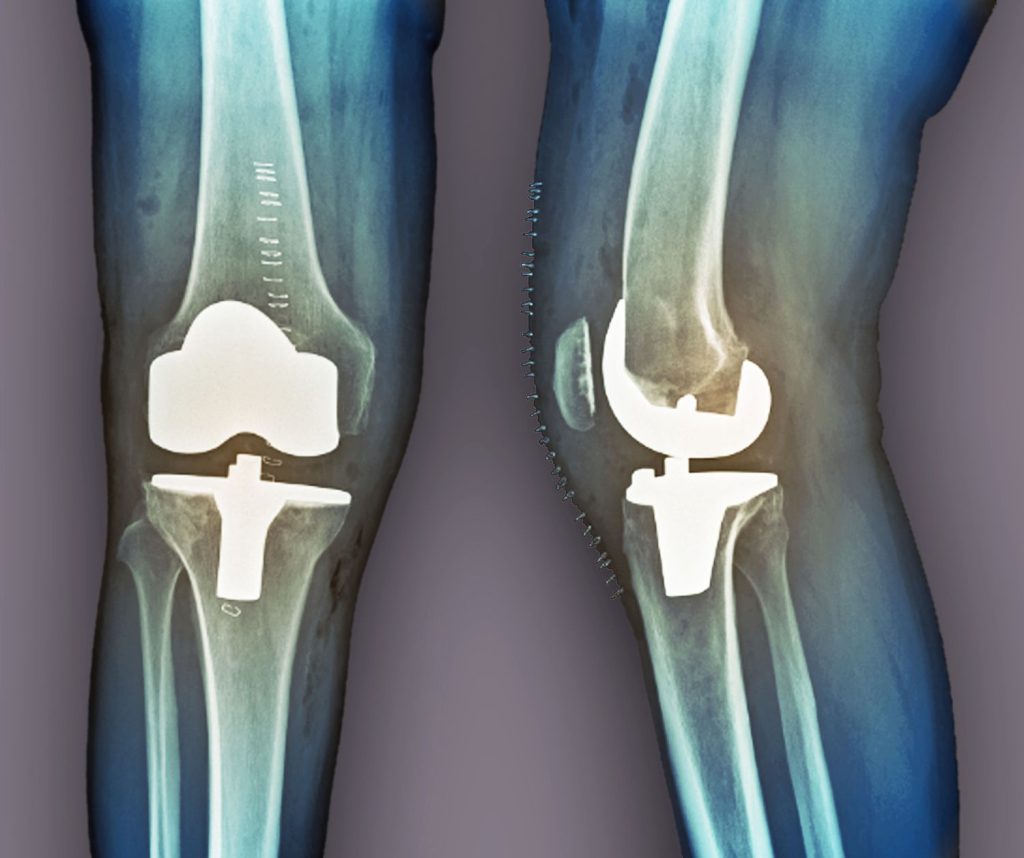

Knee replacement surgery (knee arthroplasty) is surgery to replace all or some of your knee joint. Your surgeon will replace damaged cartilage and bone with a prosthetic joint. It can take up to a year to recover fully after a knee replacement, but you’ll be able to resume some of your usual activities gradually as you heal.

جراحی تعویض مفصل زانو (آرتروپلاستی زانو) جراحی برای جایگزینی تمام یا بخشی از مفصل زانو است. جراح شما غضروف و استخوان آسیب دیده را با مفصل مصنوعی جایگزین می کند. بهبودی کامل پس از تعویض زانو ممکن است تا یک سال طول بکشد، اما میتوانید برخی از فعالیتهای معمول خود را به تدریج با بهبودی از سر بگیرید